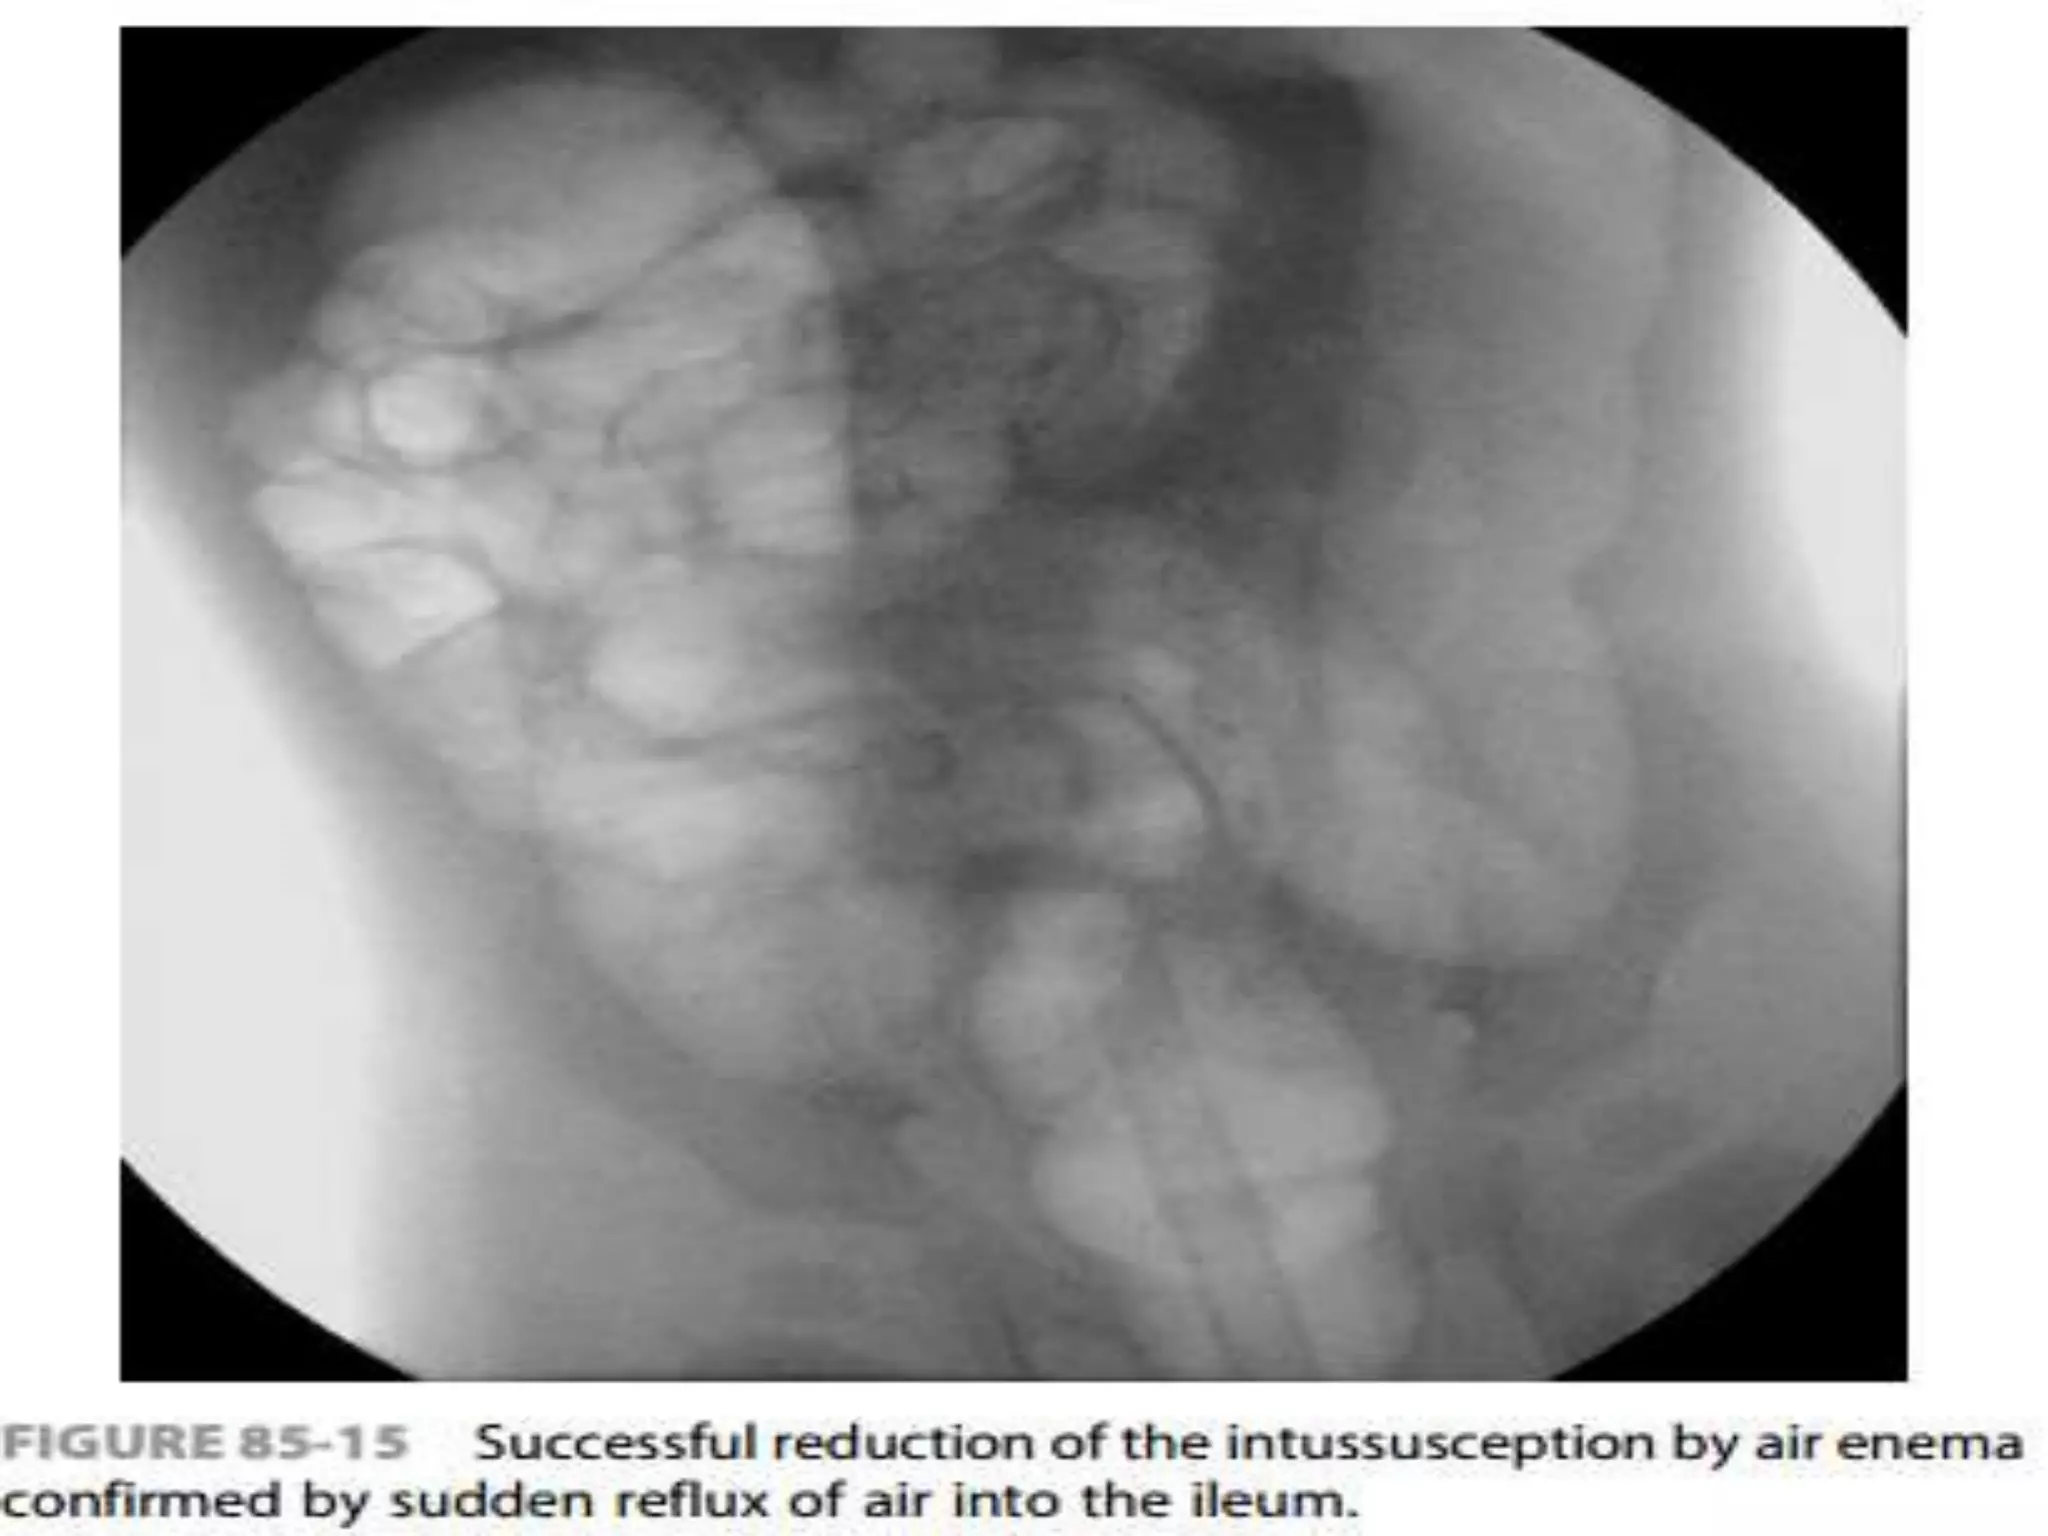

 Air should flow freely from the cecum into the

distal small bowel loops to signify complete

reduction

 Air shouldflow freely from the cecum into the distal small bowel loops to signify complete reduction  keep air pressure below a maximum limit of 120 mm Hg to avoid the risk of perforation